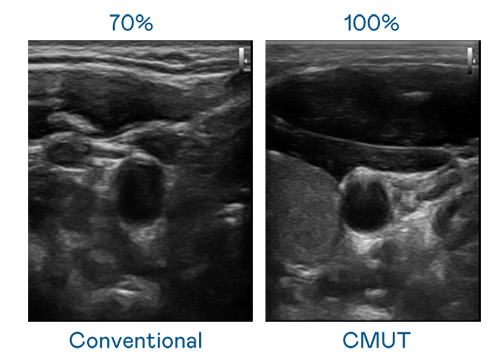

CMUT 技术是一种用电容式微机电元件来产生超音波讯号的技术。与传统 PZT 压电式技术相比,CMUT 频宽增加 30%,更宽频的超音波讯号让影像解析度大幅提升,是实现高影像品质医疗超音波扫描、促进精准医疗发展的关键技术。

大频宽带来超清晰影像

超音波影像的解析度高低,首先取决于探头能发出的讯号频宽。BG视讯 CMUT 可提供高清晰的超音波讯号,提供高频宽、高灵敏度、影像纹理细节更高的超音波影像,协助医护人员缩短影像判读时间及利用精准的医疗影像进行诊断。